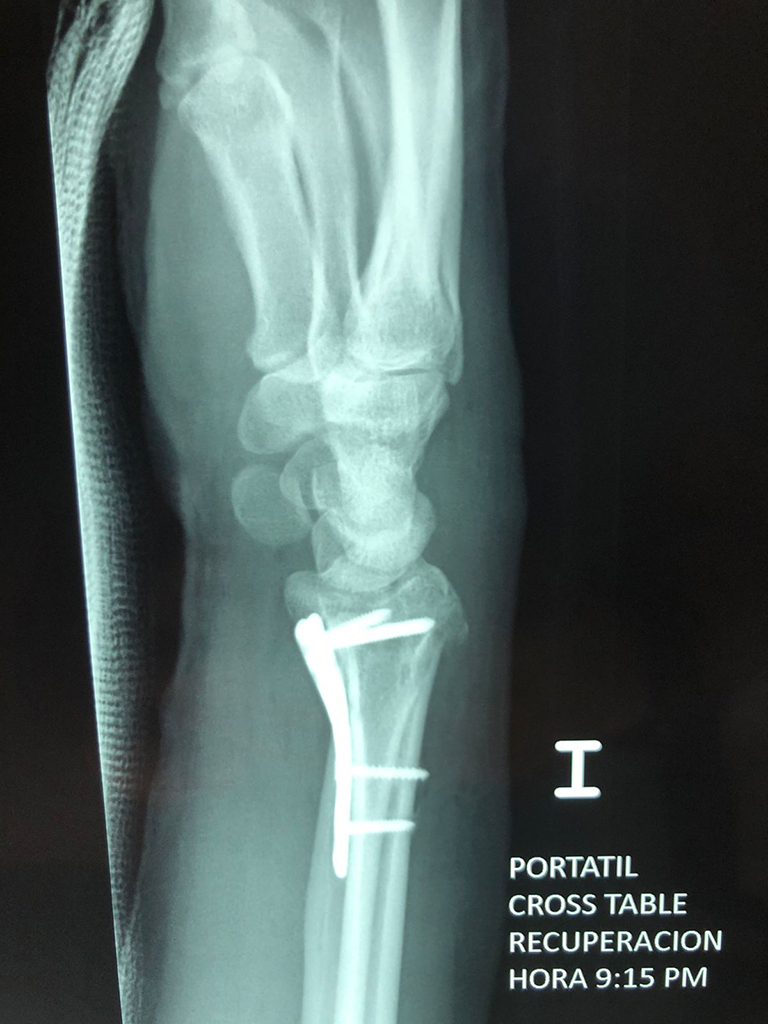

Cirugías de Calcaneo - Cirugías de Muñecas y Manos

Los procedimientos más comunes en cirugía de la mano son aquellos destinados a reparar traumatismos, incluyendo lesiones de tendones, nervios, vasos sanguíneos, y articulaciones; huesos fracturados; y quemaduras, cortes, y otros daños de la piel.